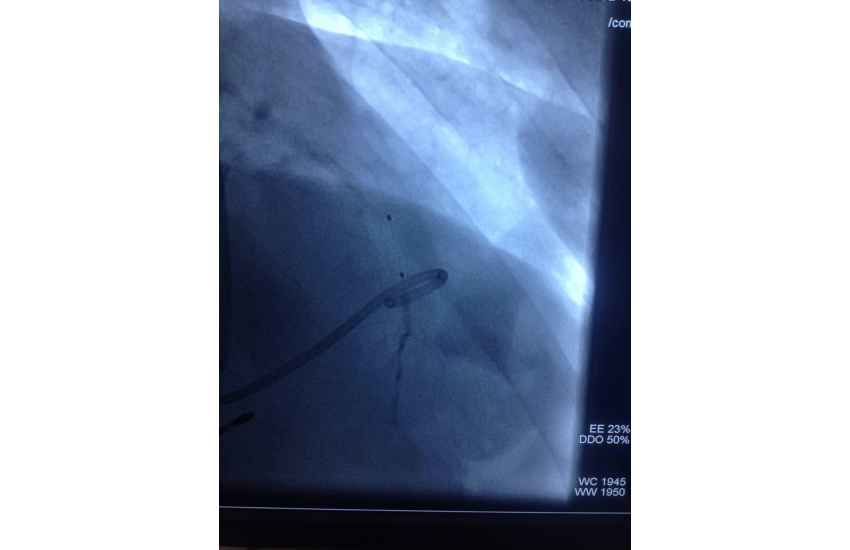

CAG revealed normal coronaries,holter shows sinus bradycardia,RBBB with LAHB,intermittent AF, TMT shows blunted chronotropic response and hypotensive response so he has been planned for PPI with back up of pacemaker patient treated with beta blockers and corderone,after 7 days of PPI,he has undergone alcohol septal ablation successfully,prior his dynaemic gradient was 50 mmhg in rest n 80 mmhg with exercise which reduced to 20mmhg after procedure. Now patient is under close follow up so will continue updating.